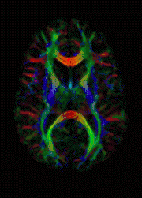

The principal application is in the imaging of white matter where the location, orientation, and anisotropy of the tracts can be measured. The architecture of the axons in parallel bundles, and their myelin sheaths, facilitate the diffusion of the water molecules preferentially along their main direction. Such preferentially oriented diffusion is called anisotropic diffusion.

The imaging of this property is an extension of diffusion MRI. If a series of diffusion gradients (i.e. magnetic field variations in the MRI magnet) are applied that can determine at least 3 directional vectors (use of 6 different gradients is the minimum and additional gradients improve the accuracy for "off-diagonal" information), it is possible to calculate, for each voxel, a tensor (i.e. a symmetric positive definite 3×3 matrix) that describes the 3-dimensional shape of diffusion. The fiber direction is indicated by the tensor's main eigenvector. This vector can be color-coded, yielding a cartography of the tracts' position and direction (red for left-right, blue for superior-inferior, and green for anterior-posterior).[45] The brightness is weighted by the fractional anisotropy which is a scalar measure of the degree of anisotropy in a given voxel. Mean diffusivity (MD) or trace is a scalar measure of the total diffusion within a voxel. These measures are commonly used clinically to localize white matter lesions that do not show up on other forms of clinical MRI.[46]